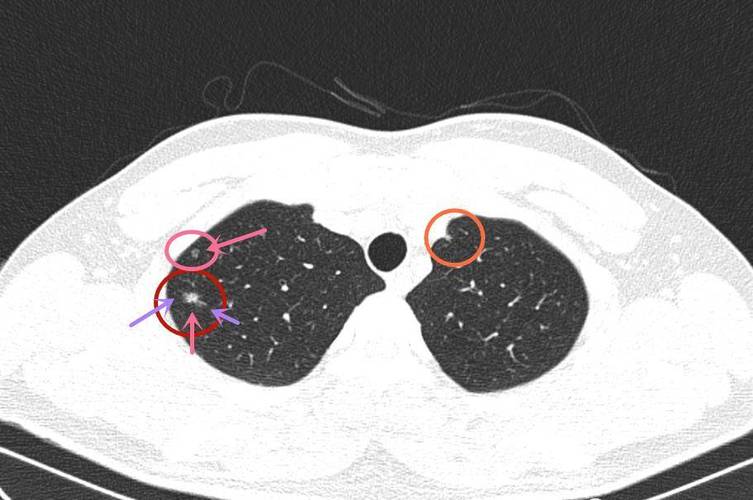

左中肺野外带可疑病灶

2、左肺下叶外侧段结节影增强扫描后病灶未见明显强化,病灶界限清楚。余肺实质未见明显渗出或占位性病变。两肺门无增大,气管及诸支气管通畅。双肺门及纵隔未见肿大淋巴结。双侧胸腔未见明显异常。心影未见明显异常。肝脏密度减低。